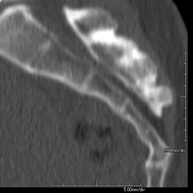

Prueba radiológica que consiste en obtener imágenes del oído de alta definición anatómica (conducto auditivo interno y externo, tímpano, huesecillos del oído), mediante el empleo de un equipo de TC (Tomografía Computarizada). Indicaciones: trastornos de la audición, cuadros vertiginosos, mareos, acúfenos (pitidos). - TC Dental

Prueba radiológica que consiste en obtener imágenes del hueso peñasco del temporal (oído interno, medio y externo) de alta definición anatómica mediante el empleo de un equipo de TC (Tomografía Computarizada). Indicaciones: pérdida de audición súbita o crónica, cuadros vertiginosos, mareo, malformaciones congénitas. - Angio – TC Troncos Supraaórticos